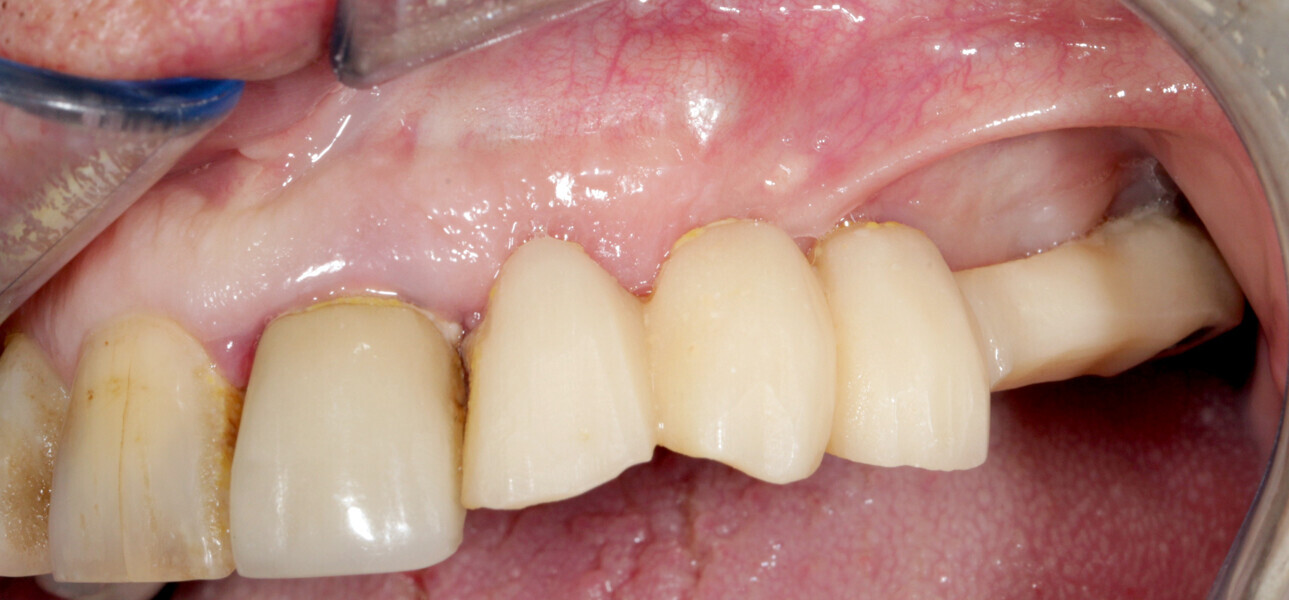

A 62-year-old patient with a bridge from tooth #21 to tooth #27 requiring replacement, teeth #21, 23, 24 and 27 with abutments and the crown of #22, 25 and 26 missing, was treated. The ridge of tooth #22 exhibited a transverse bone insufficiency which would have allowed the placement of an implant, but the aesthetic outcome would have been unsatisfactory (Fig. 10). First, the bridge of tooth #24 was sectioned distally and the root of tooth #27 extracted. After a two-month healing period, the patient was treated with simultaneous extraction, implantation and aesthetic restoration. The bridge was sectioned distally at tooth #21, a full thickness flap was elevated and the teeth #23 and 24 were extracted, allowing the bone defect at tooth #22 to be assessed (Fig. 11). Implants were placed into sites #22, 24 and 27. The root of tooth #23 allowed us to compensate for the bone defect and achieve a satisfactory aesthetic result. The root was prepared as described. The radicular graft was fixated away from the ridge, the edges of the graft in contact with the alveolar bone (Fig. 12). The spaces between the ridge, the graft and the alveoli were filled with a synthetic, hydroxyapatite-based biomaterial, the flap was stretched and sutured around the healing abutments, an impression was taken, and a temporary prosthesis from implant #22 to 27 was made during the day by the laboratory and fitted the same evening. The stitches were removed on the tenth day and the bridge after two months to check for the successful osseointegration of the implants. The osteosynthesis screws were not removed in this case because they were not visible under the gingiva (Figs. 13 & 14). A CBCT assessment was performed after six months to check that the graft had taken successfully. Finally, our colleague fitted the definitive prosthesis.

Fig. 21: Fitting of the definitive prosthesis.